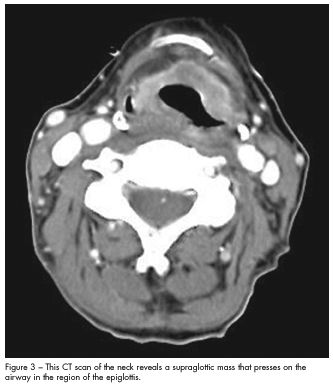

Because of her dysphagia, a videofluoroscopic swallow study was done, which suggested aspiration. This prompted a triple endoscopy that revealed an exophytic mass on the epiglottis along with right vocal cord paralysis. A CT scan of the neck (Figure 3) showed a supraglottic mass that impressed on the airway in the region of the epiglottis. CT-guided fine needle aspiration of the cavitary lesion revealed pulmonary epithelial cells, histiocytes, and muscle fibers suggestive of aspiration. There were no malignant cells.

A diagnosis of supraglottic squamous cell carcinoma stage T4aN0Mx complicated by bilateral cavitary aspiration pneumonia was made. The patient was treated with ampicillin/sulbactam to which she responded well, and she had a tracheostomy followed by a percutaneous endoscopic gastrostomy. A PET scan was scheduled prior to the initiation of radiation therapy.